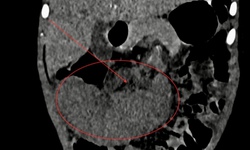

BV Đa khoa Ninh Thuận phẫu thuật thành công ca u tuyến cận giáp hiếm gặp

Y tế - 20/10/2025 11:26SKĐS - Bệnh viện Đa khoa Ninh Thuận vừa thực hiện thành công ca phẫu thuật bóc tách khối u tuyến cận giáp hiếm gặp cho bệnh nhân nam 46 tuổi, đánh dấu thêm một bước tiến trong năng lực phẫu thuật nội tiết của bệnh viện tuyến tỉnh.